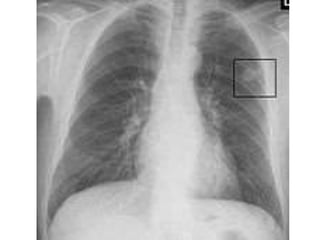

Nódulo pulmonar 8-30 mm

ENFOQUE PARA PACIENTES CON NPS

Etiologías BENIGNAS Granulomas infecciosos Hamartomas Absceso Quiste hidatídico Neumoníaredonda MAV Sarcoidosis Wegener MALIGNAS Carcinoma primario de pulmón Tumor carcinoides Linfoma Metástasis solitaria Sarcoma Neurofibroma

Nódulo pulmonar 8-30mm Calcificación benigna Estabilidad por 2 años sí No mayor evaluación no Riesgo quirúgico aceptable sí Riesgo de cáncer bajo (<10%) Riesgo de cáncer intermedio (10-60%) Riesgo de cáncer alto (>60%) Seguimiento con TAC 3-6-9-12-18-24 meses Cirugía videotorascoscópica Biopsia por congelación Resección PET, TC con Cte, PAAF guiada por TC, Broncoscopia - + Individualizar opciones no N Engl J Med 2003;348:2535-42. ENFOQUE PARA PACIENTES CON NPS